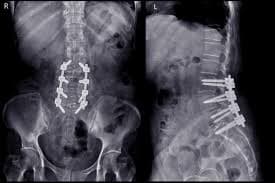

Revision surgery has mixed results, and it is typically reserved for cases where a specific, correctable structural problem has been identified and other treatments have failed. Repeat surgeries have a diminishing likelihood of successful outcome. Each subsequent surgery has a 50%, 30%, 15%, and 5% chance of success respectively. As a final option, spinal cord stimulation may be considered. This is a minimally invasive procedure where a small device is implanted to send electrical impulses to the spinal cord, which can block the pain signals from reaching the brain.